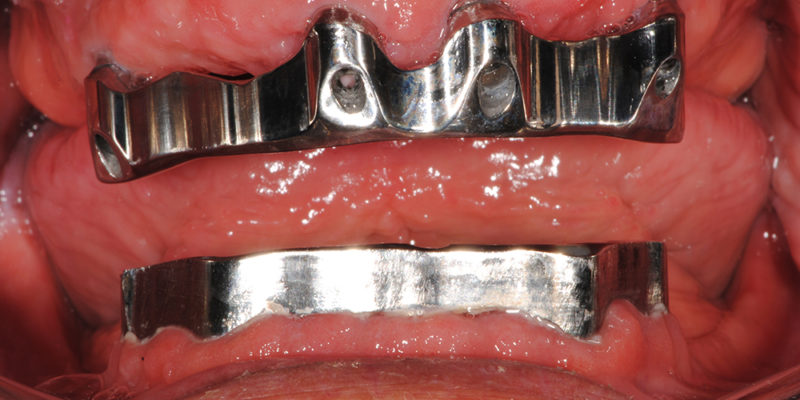

Ripristino dell’arcata superiore ed inferiore su overdenture su barra